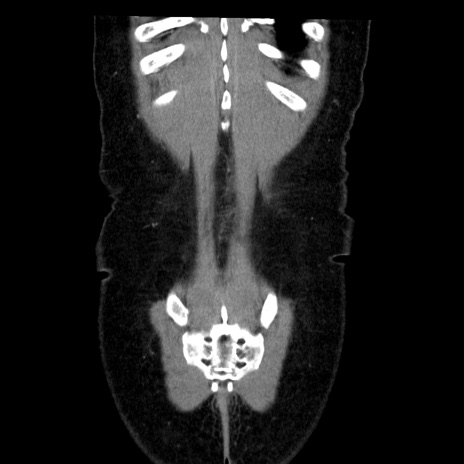

矢状断像

【症例】50歳代女性

【主訴】下腹部痛

【現病歴】本日朝より下痢2回あり。 昼食を食べた後、嘔吐3回、下腹部痛認め、症状軽快せず、当院救急搬送。

最終食事:本日昼(生ものなし)。 昨日の夜、刺身を食ぺたとのこと。周囲に同様の症状の者なし。普段、排便は毎日あるとのこと。

【既往歴】卵巣癌術後(8年前に当院で卵巣摘出)

【身体所見】 意識清明、腹部:平坦、腸蠕動音→、やや硬、下腹部自発痛・圧痛あり、反跳痛あり、筋性防御なし。

【データ】WBC 16000、CRP 0.01